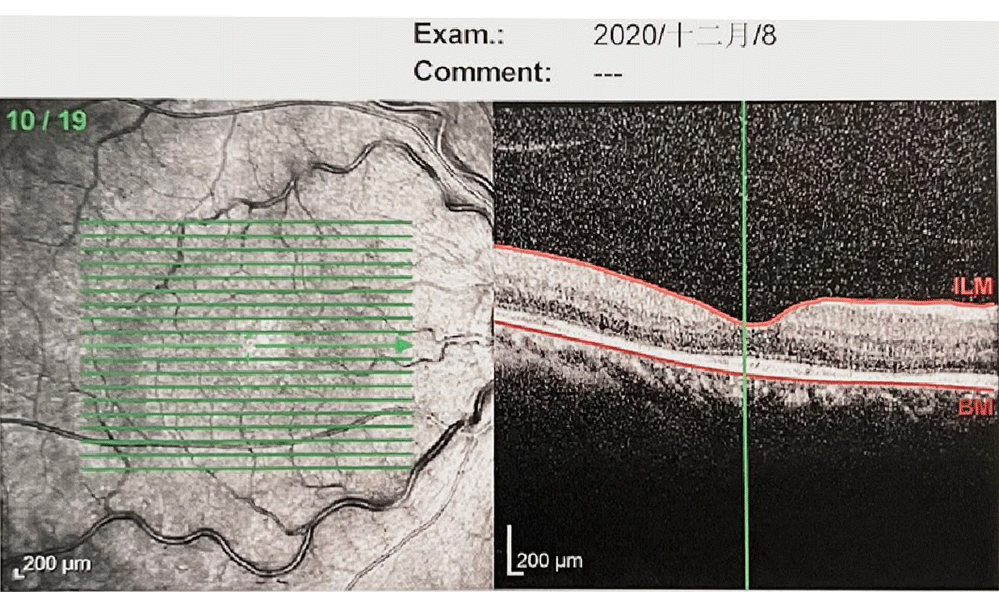

▌OCT:

右眼底视网膜弥漫性增厚,黄斑囊样水肿,视网膜下可见积液

• 病例特点:患者为中年男性,有高血压、糖尿病基础疾病史;右眼视力下降半年,曾用中药治疗、2次抗VEGF治疗;右眼基线视力为0.2,右眼眼底检查见视盘边界模糊,视网膜动脉硬化,静脉迂曲扩张。OCT示右眼黄斑囊样水肿明显,隆起高,结果提示视网膜中央静脉阻塞(CRVO);结合患者病史及眼科检查,考虑右眼视力下降原因是视网膜中央静脉阻塞导致的黄斑囊样水肿(CME),而非糖尿病性视网膜病变所致。

• 2020年2月11日:行右眼抗VEGF治疗(雷珠单抗)

第1次抗VEGF治疗后13天,2020年2月25日

自觉视力有提高

视力:VOD 0.8

眼压:15mmHg

嘱其1个月后复查